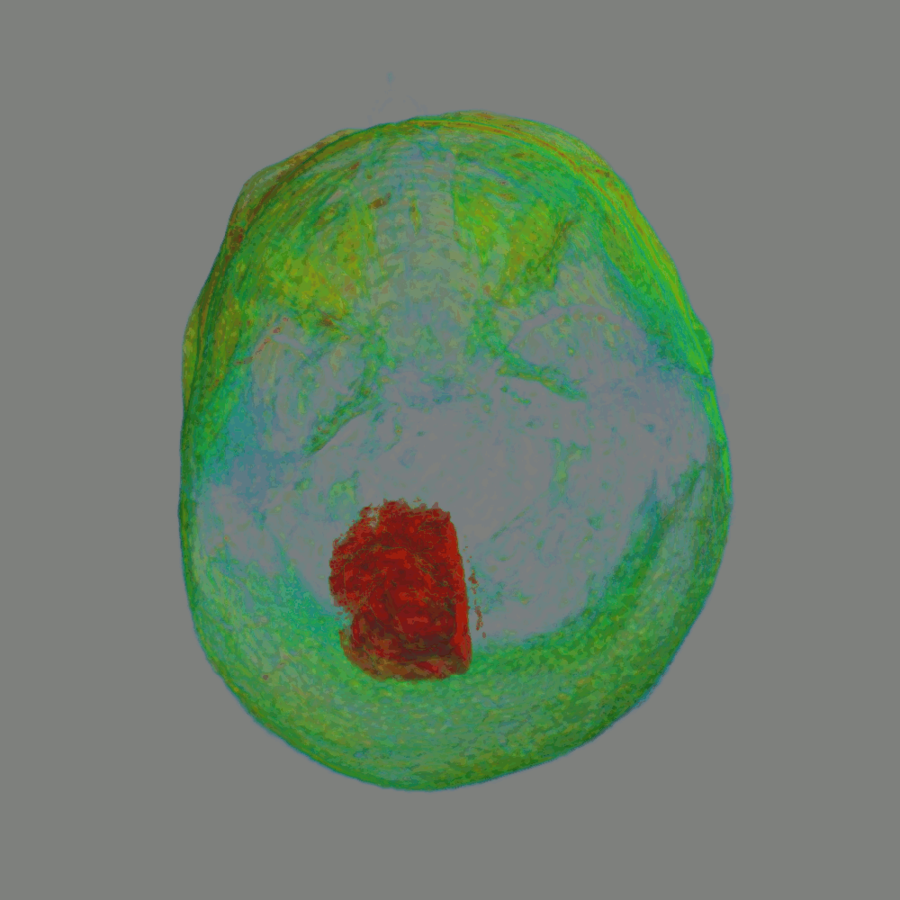

MRI

• Skull extraction

• Background Tumor segmentation

• Tumor features extraction

• Tumor classification